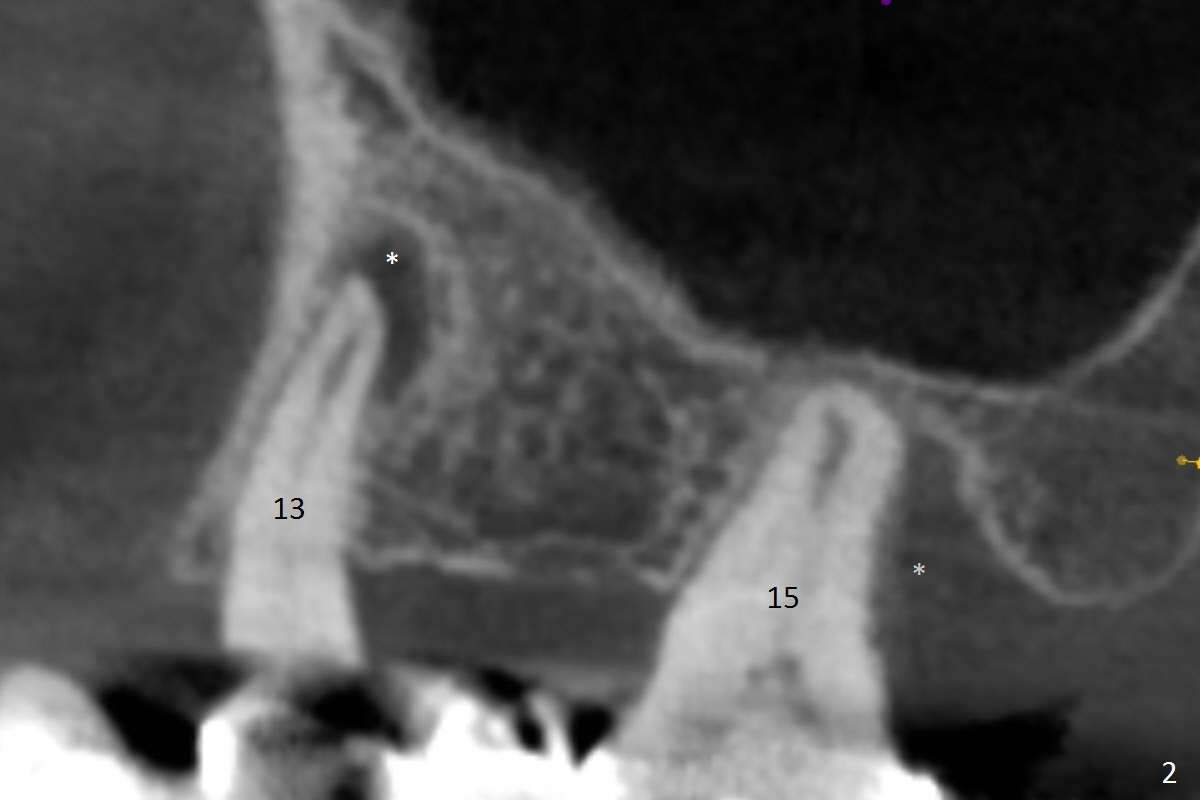

While the 64-year-old woman is undecided on the lower right quadrant treatment, she has had periodic pain and swelling in the upper left quadrant (Fig.1). CBCT sagittal sections show periapical radiolucency at #13 and bone loss distal to #15 palatal root (Fig.2,7). Endodontic treatment is the 1st option to save the long bridge (#9-15, Fig.1).

More thorough option is to section between #11 and 12, remove #13 and 15 retainers and determine salvageability of #13 and 15 abutments. Place implants between #12 and 15 if necessary (Fig.3-6 coronal sections; B: buccal).